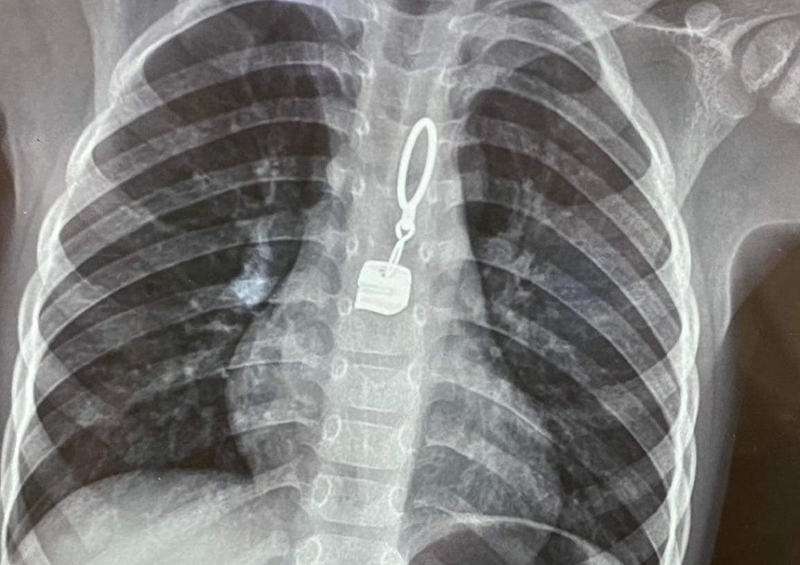

Nghẽn dị vật thực quản cũng có thể gây ra tình trạng đau dọc theo đường đi của thực quản. Khi các dị vật như thức ăn, xương,... bị mắc kẹt trong thực quản gây khiến người bệnh cảm thấy khó nuốt thức ăn hoặc nước bọt, gây đau và cảm giác khó chịu tại khu vực thực quản bị vướng, cảm thấy đau khi nuốt. Điều này có thể xảy ra ở cả trẻ em và người lớn, không nên chủ quan.

Trẻ nhỏ dễ bị nghẹn dị vật thực quản do tính hiếu động, thường hay ngậm và nuốt các vật nhỏ như cúc áo, đồng xu,... Trường hợp người lớn bị nghẹn dị vật do thói quen ăn uống không cẩn thận, không nhai kỹ, dẫn đến việc hóc xương.